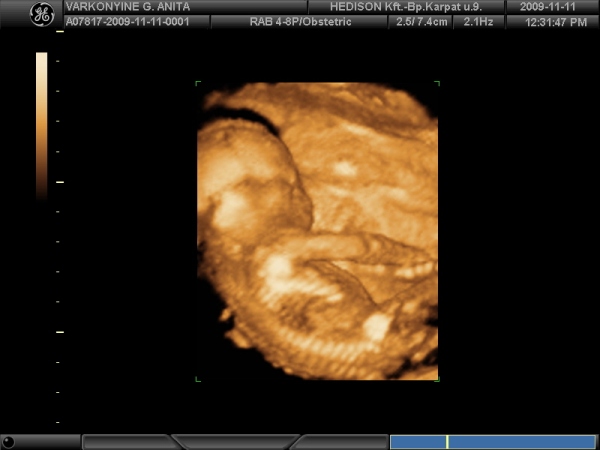

Amúgy mi a 25. hétben vagyunk, és még nem tudjuk, hogy mire számítsunk, mert a 16 hetes UH-n a babó a világért sem akart megfordulni és a lábától kezdve mindenét mutogatta, csak a lényeget nem.